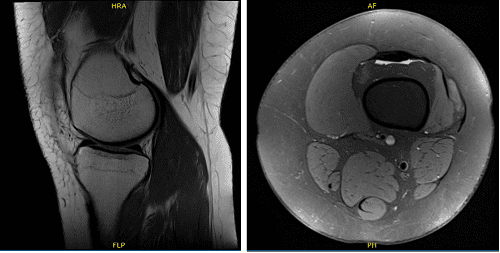

We agreed to have an MRI which showed status post meniscal repair of bucket-handle tear seen previously with appearance is recurrent tear and disruption of anterior horn associated with displacement of a large flap and focal disruption of posterior horn into proximity of tibial attachment.

Postsurgical changes are present at the meniscocapsular junction and through the subcutaneous tissue. Arthroscopic portals are also visualized to infrapatellar fat. Mild lateral compartment degenerative disease and small joint effusion were also observed.